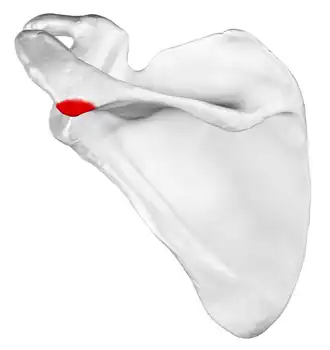

![]() Left scapula, posterior view. Acromion shown in red. | |

In human anatomy, the acromion (from Greek: akros, "highest", ōmos, "shoulder", pl.: acromia) or summit of the shoulder is a bony process on the scapula (shoulder blade). Together with the coracoid process, it extends laterally over the shoulder joint. The acromion is a continuation of the scapular spine, and hooks over anteriorly. It articulates with the clavicle (collar bone) to form the acromioclavicular joint.[1]

The acromion forms the summit of the shoulder and is a large, somewhat triangular or oblong process, flattened from behind forward. It projects laterally at first, then curves forward and upward to overhang the glenoid fossa.[2] It starts from the base of acromion which marks its projecting point emerging from the spine of scapula.[3]